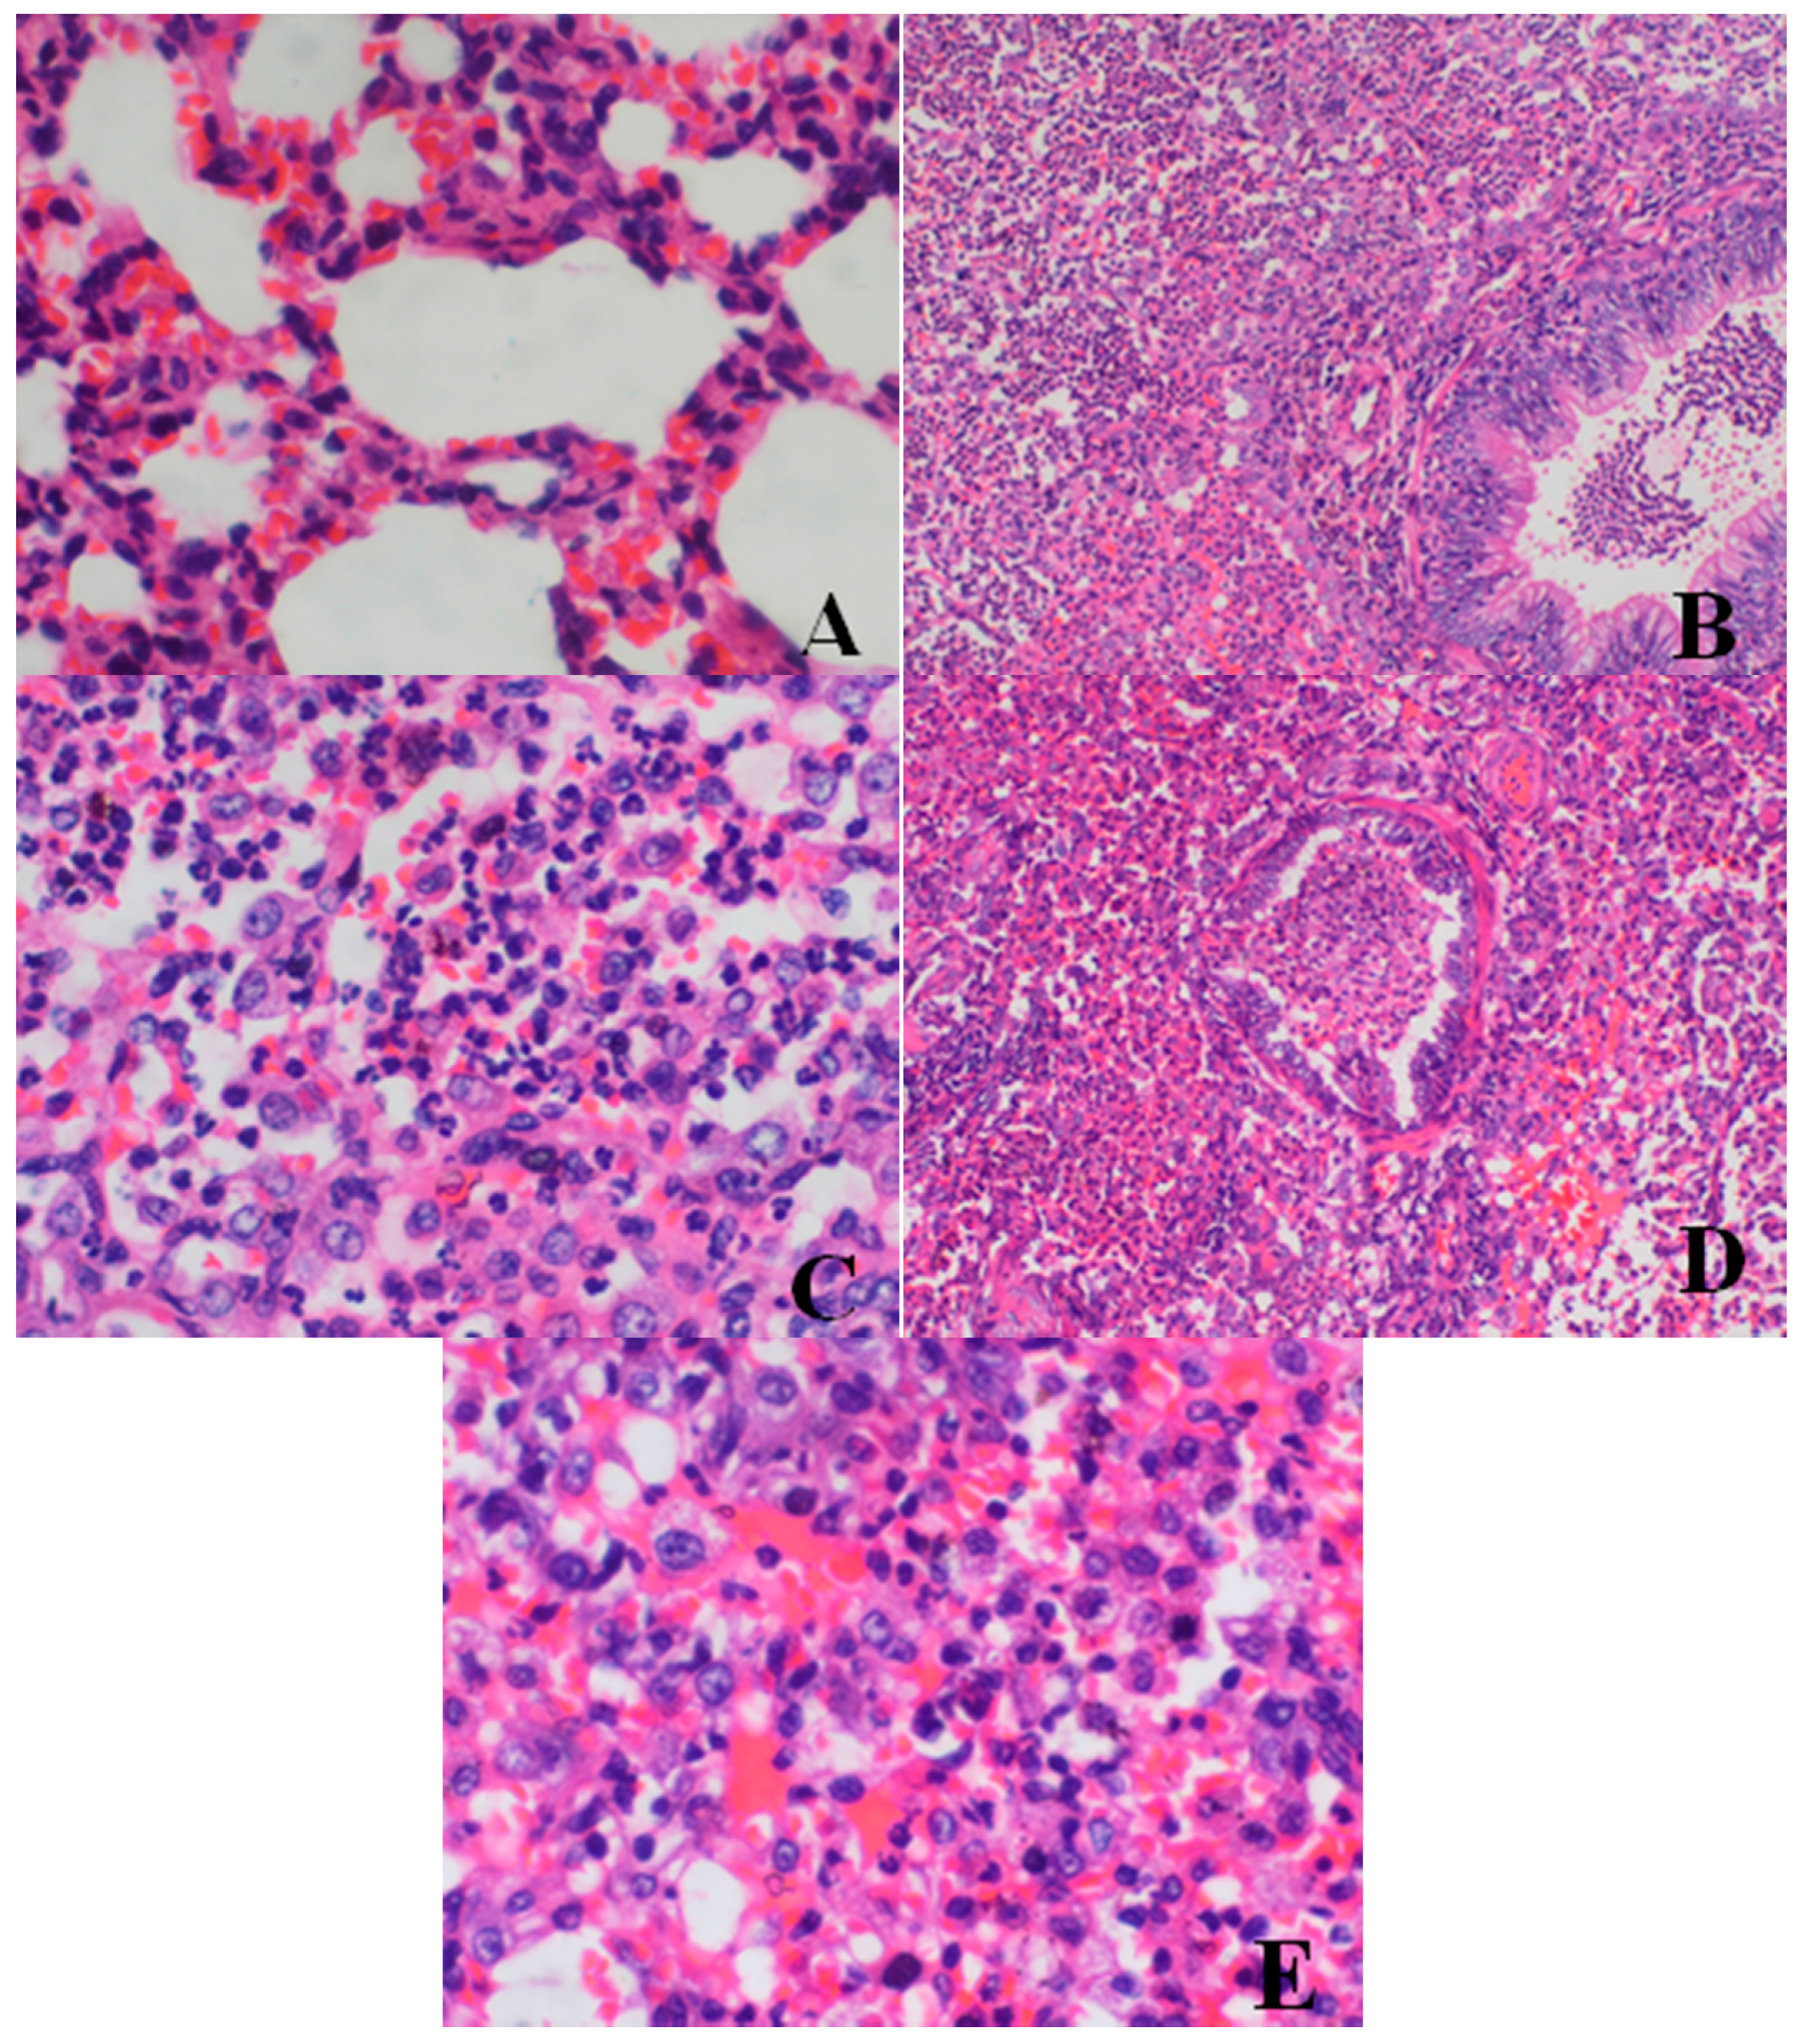

Histopathological Findings

| Organ | Findings | Dose (mg/kg/day) | ||||

|---|---|---|---|---|---|---|

| 0 | 5 | 20 | 40 | 80 | ||

| Lung | large confluent bronchopneumonia | 0/4 | 0/4 | 0/4 | 2/4 | 2/4 |

| Bone marrow of sternum | decrease in hematopoietic cell numbers | 0/4 | 0/4 | 0/4 | 2/4 | 3/4 |

| Testis | Reduction in numbers and types of spermatogenic cells | 0/2 | 0/2 | 0/2 | 2/2 | 2/2 |

| Epididymis | lack of mature sperm and secretions in the epididymal lumen as well as decrease of epididymal lumen size | 0/2 | 0/2 | 0/2 | 2/2 | 2/2 |

| Prostate | reduction in numbers and size, thinner epithelium, narrowing of the glandular cavity of prostatic acini | 0/2 | 0/2 | 0/2 | 2/2 | 2/2 |